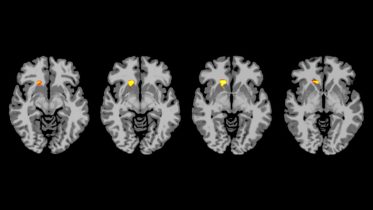

The brains of people with type 1 diabetes react differently to low blood sugar compared with healthy adults, say Yale researchers. The findings of their...